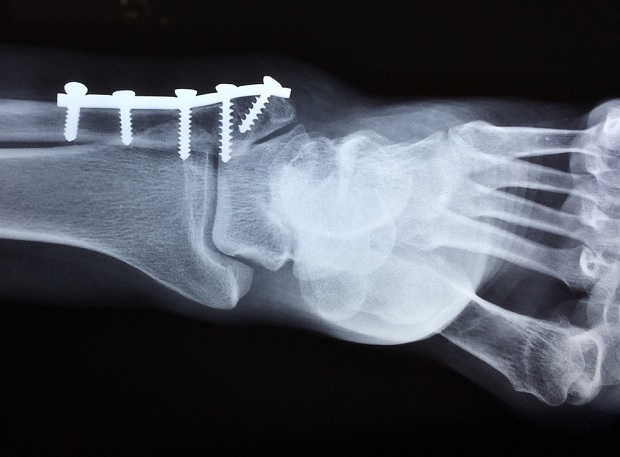

Desarrollan un método para que los huesos de los adultos se reparen solos, como en los bebés

Los bebés y los ratones recién nacidos pueden curar de forma natural los daños en los huesos que forman la parte superior del cráneo, pero esta capacidad se pierde en los adultos. Sin embargo, ¿es posible recuperarla?

Ahora, en un nuevo estudio publicado en 'Proceedings of the National Academy of Sciences', investigadores de la Universidad de Pittsburgh, en Estados Unidos, han desarrollado un novedoso método que fomenta la regeneración ósea en ratones sin implantar tejido óseo ni biomateriales.

La técnica utiliza un dispositivo similar a un alambre de ortodoncia empleado para realinear los dientes para estirar cuidadosamente el cráneo a lo largo de sus suturas, activando las células madre esqueléticas que residen en estas costuras ondulantes. En ratones adultos, la técnica reparó daños en el cráneo que de otro modo no se habrían curado por sí solos.

En ratones --que tienen un desarrollo craneal muy similar al de los humanos--, los investigadores utilizaron un dispositivo denominado de distracción ósea para aplicar cuidadosamente una fuerza de tracción controlada a los huesos calvariales, lo suficientemente fuerte como para ensanchar ligeramente las suturas pero no lo suficiente como para provocar una fractura.

Los tratamientos actuales para los daños en el cráneo suelen consistir en injertos óseos o en la implantación de biomateriales que actúan como andamios para la regeneración ósea, pero estos enfoques no siempre son eficaces y conllevan riesgos, tal y como ha advertido Intini.

Los investigadores están estudiando cómo utilizar sus hallazgos en terapias novedosas para las personas, no solo para curar lesiones craneales, sino también fracturas de huesos largos como el fémur.

Los dispositivos de distracción ósea ya se emplean para tratar ciertas afecciones, como la craneosinostosis, un defecto congénito en el que los huesos calvarios se fusionan demasiado pronto, por lo que ampliar esta técnica para favorecer la regeneración ósea podría ser uno de los futuros objetivos de los ensayos clínicos. Intini y su equipo también están investigando métodos no mecánicos para activar las células madre esqueléticas, como los medicamentos.